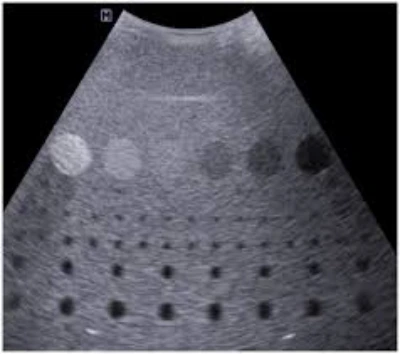

A manutenção de transdutores de ultrassom é essencial para preservar a qualidade das imagens e a precisão nos exames clínicos .

Inclui inspeções, limpeza, calibração e reparos dos sensores responsáveis pela captura das imagens.

Esse cuidado técnico evita falhas, prolonga a vida útil dos transdutores e permite a continuidade do atendimento em clínicas e hospitais.

A manutenção adequada assegura resultados confiáveis, segurança operacional e desempenho constante dos aparelhos, fortalecendo a eficiência dos procedimentos médicos e a qualidade do diagnóstico em diferentes especialidades.